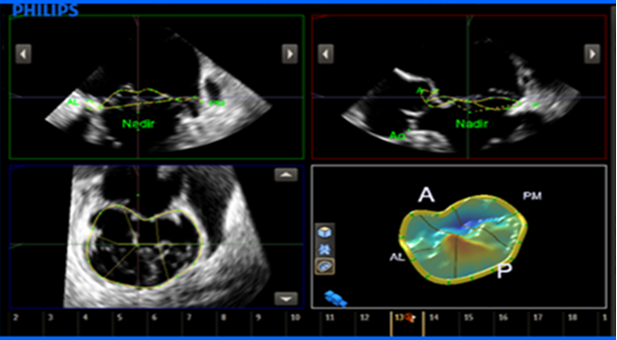

通过MVQ分析得出的MV几何体的3D参数。